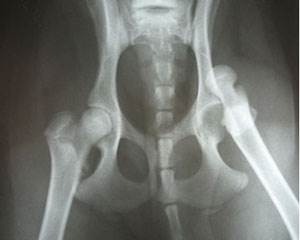

Вывих тазобедренного сустава (ТБС) – часто встречающаяся травма у собак.

Чаще вывих (подвывих) ТБС встречается у собак средних и крупных пород, в основном в результате предрасположенности этих пород к дисплазии тазобедренного сустава.

Тазобедренный сустав принимает на себя основную часть нагрузки при локомоции, служит передатчиком толчков при беге и прыжках. У здорового животного суставные поверхности ТБС – суставная впадина на тазовой кости и головка бедра, – конгруэнтны (соответсвенны) друг другу, хрящи не подвергаются разрушению, прочность сустава очень велика. Поэтому вывих ТБС у здоровых животных без врожденных патологий возникает только в случае серьезных происшествий:

Большая часть собак с такой травмой – собаки с врожденной дисплазией тазобедренного сустава. Даже при легкой степени дисплазии суставные поверхности неконгруэнтны, и риск “вылетания” сустава их вертлюжной впадины гораздо выше, чем у здоровых животных. В запущенных случаях дисплазии собака может получить вывих при обычной ходьбе или игре.

Если Вы наблюдаете вышеперечисленные симптомы, необходимо срочно доставить питомца в клинику. Нельзя пробовать вправить вывих самостоятельно или давать анальгетики! Если собаку обезболить, она перестанет чувствовать боль, что может усугубить травму. Вправлять вывих можно, только проведя рентгенографическое исследование и подтвердив диагноз – схожие симптомы также могут наблюдаться у перелома таза или шейки бедренной кости и ряда других травм. При переломе самостоятельные попытки “вправить” лапу часто приводят к необходимости ампутации конечности. Даже если у собаки действительно вывих, его вправление очень болезненно, и не может проводиться без анестезии.